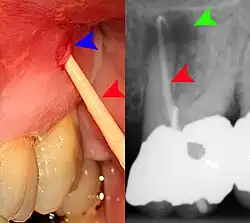

Decay (green) with apical abscess (blue) -

Gutta-percha point indicating abscess origin